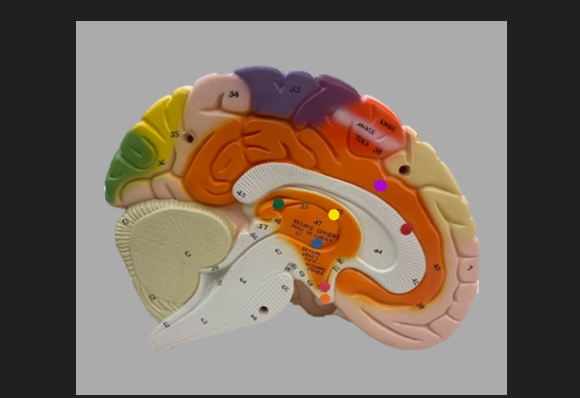

frontal lobe

blue dot

longitudinal fissure

dark green dot

precentral gyrus

pink dot

postcentral gyrus

yellow dot

central sulcus

white dot

parietal lobe

light green dot

Broca’s Area

red dot

Wernicke’s Area

orange dot

occipital lobe

blue dot

parieto-occipital sulcus

blue dot

olfactory tract

red dot

corpora quadrigemina

dark green dot

cerebral aqueduct

blue dot

cerebral penduncles

pink dot

pons

orange dot

medulla oblongata

yellow dot

mammillary body

red dot

corpus callosum

dark green dot

pineal gland

yellow dot

epithalamus

blue dot

thalamus

orange dot

optic chiasm

pink dot

infundibulum

purple dot

cingulate gyrus

yellow dot

pituitary gland

dark green dot

pyramids

red dot

olives

blue dot

optic tract

purple dot

midbrain

green dot

folia

orange dot

arbor vitae

yellow dot

fourth ventricle

red dot

vermis

blue dot

hypothalamus

pink dot

cerebral hemispheres

yellow dot

lateral sulcus

red dot

lateral ventricles

blue dot

hippocampal gyrus

green dot

olfactory tract